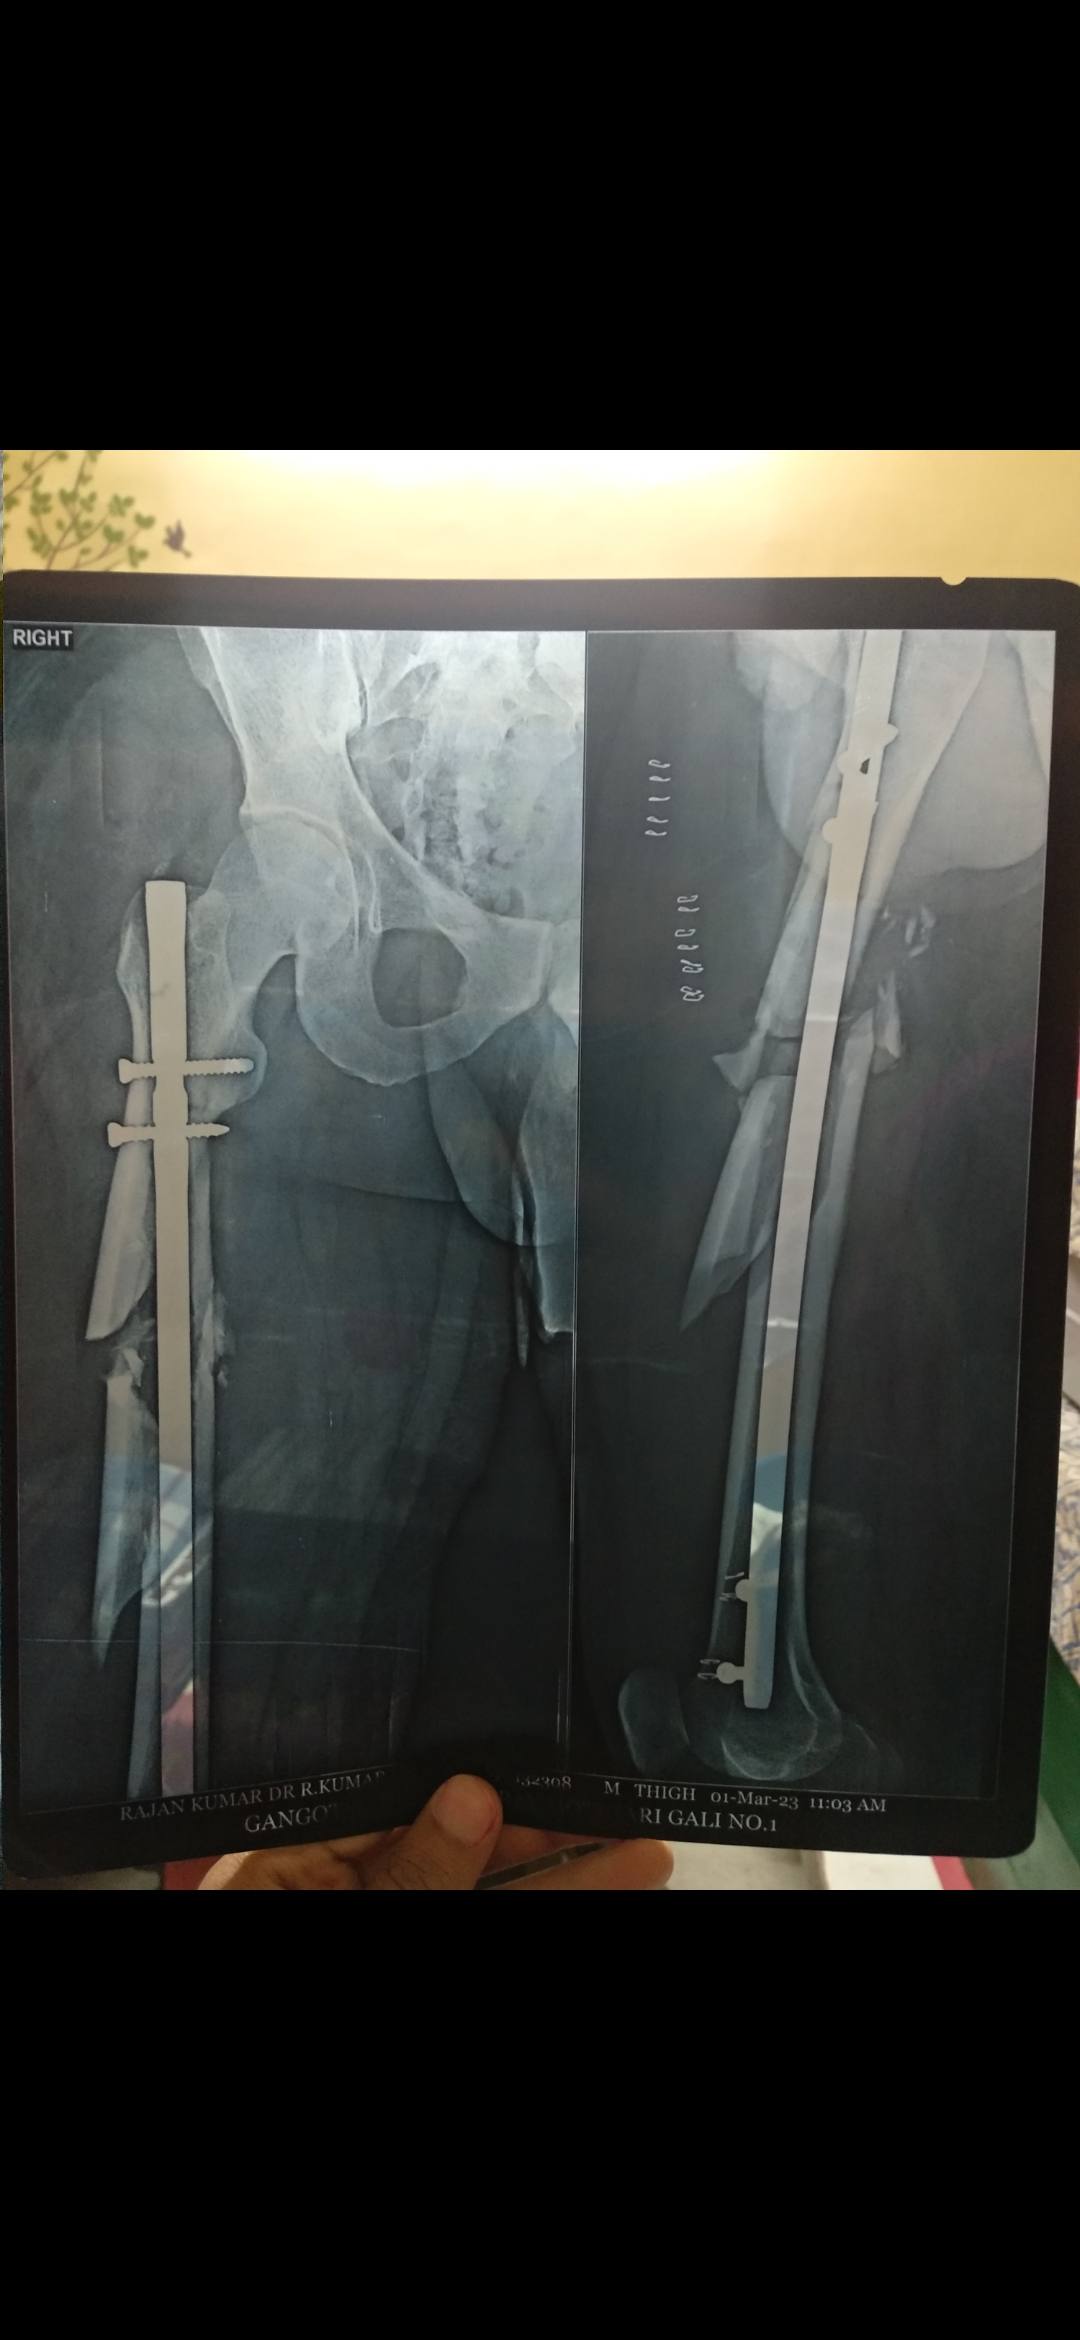

Femor bone

Sir mere fumer bone fracture ho gya tha, jiska operation bhi hua h, ye bta sakte ki kb tak thik honge or exercise kr skte h???